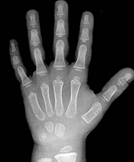

Hand bone age AI

Predict hand bone age. In a small test of 129 random Stanford clinical cases, AI predicted age within 12 months.

C. Fang, S. Baig, D. Larson, M. Fadell, B. Do